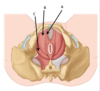

Name structures A-D

A = urethra

B = prostate

C = vagina

D rectum